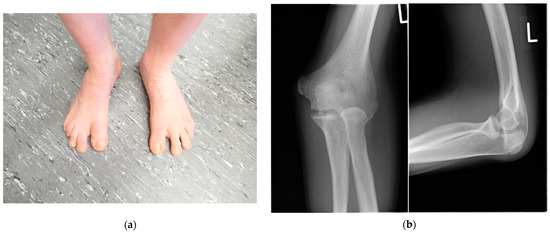

His dizygotic twin brother (patient VI.2.) presented with a slightly limited range of motion of the elbow joints. Pronation was limited by 10°, and extension of the elbow was limited by 30° (Ext/Flex 0-30-140). The range of motion of his thumbs also appeared to be slightly limited. His halluces were broad and showed valgus deviation (Figure 3a). In childhood, a bilateral hallux valgus deformity was surgically corrected; and in adolescence, a calcaneonavicular coalition was surgically corrected on both feet. He also has pectus carinatum and bilateral absence of skin creases over the distal interphalangeal joints, and he reported lumbar back pain.

Figure 3.

Patient VI.2. (a) Photograph of his feet after surgical correction of hallux valgus: note the broad and still valgus deviated halluces and sandal gaps. (b) The radiographs of the left elbow showed a dysplastic distal humerus with a tiny trochlea and dysplastic olecranon and a dysplastic convex radial head. (c) A computed tomography of the elbow depicted the malformation (upper row: coronal view, lower row: sagittal view). (d) Radiographs of the hands displayed a dysplastic first metacarpal base and head, flattening of the heads of metacarpal 3 and 4 as well as synostosis of the middle and distal phalanges of the fifth fingers. (e) An MRI of the lumbar spine revealed a partial posterior vertebral synostosis marked by arrows of L3 and L4 (upper row: T1-weighted images, lower row: T2-weighted images).

Radiographs of the left elbow showed a dysplastic distal humerus with a tiny trochlea and dysplastic olecranon and a dysplastic convex radial head (Figure 3b). A computed tomography of the elbow depicted the malformation (Figure 3c). Radiographs of the hands displayed a dysplastic first metacarpal base and head, flattening of the heads of metacarpals 3 and 4 as well as synostosis of the middle and distal phalanges of the fifth fingers (Figure 3d). The radiographs of the feet before correction of the calcaneonavicular coalition displayed a coalition between the anterior processus calcanei and the os naviculare. An MRI of the spine showed partial lumbar vertebral synostosis L3-L4 (Figure 3e).